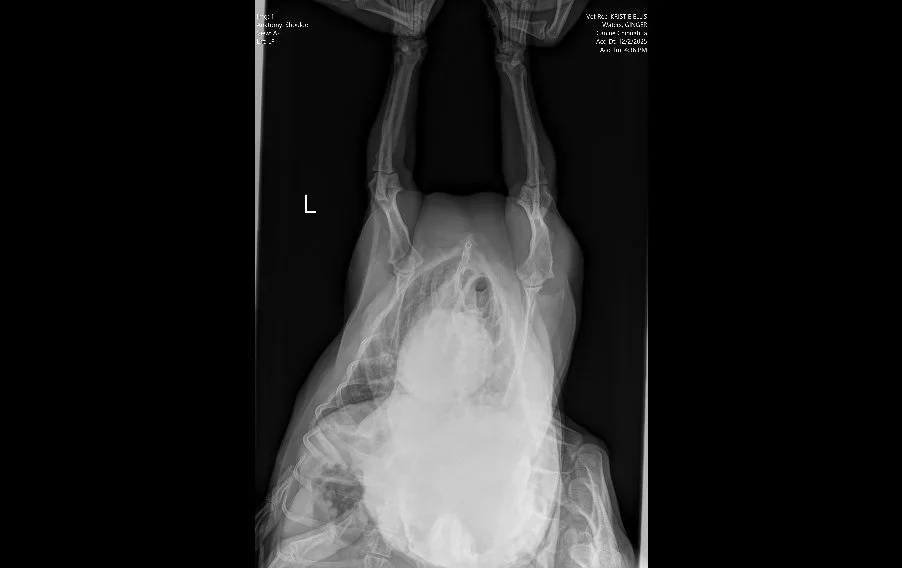

Image 1. Ventrodorsal radiograph of the thorax and forelimbs.

Radiographs (Images 1–4) of the left forelimb, including the carpus, elbow, and shoulder identified:

• Mild degenerative joint disease (arthritis)

• Decreased shoulder joint space

• No fractures, masses, or bone lysis

Based on these findings, Ginger was treated for osteoarthritis. However, her clinical progression did not match the imaging results.

👉 This mismatch is critical. Radiographs are excellent for evaluating bone, but they cannot assess nerve roots, the spinal cord, or most soft tissue structures.